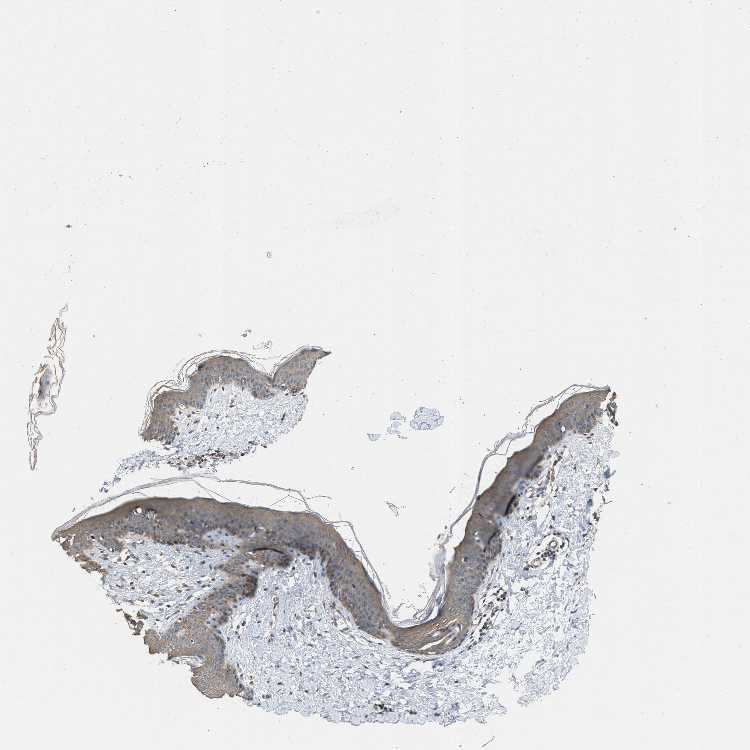

SKIN 1 - Antibody stainingi

Antibody staining in the annotated cell types in the current human tissue is reported as not detected, low, medium, or high, based on conventional immunohistochemistry profiling in selected tissues. This score is based on the combination of the staining intensity and fraction of stained cells.

Each image is clickable and will lead to virtual microscopy that enables deeper exploration of all samples and also displays staining intensity scores, fraction scores and subcellular localization as well as patient and tissue information for each sample.

Antibody CAB017716

Langerhans Not detected

Fibroblasts Medium

Keratinocytes Medium

Melanocytes Medium